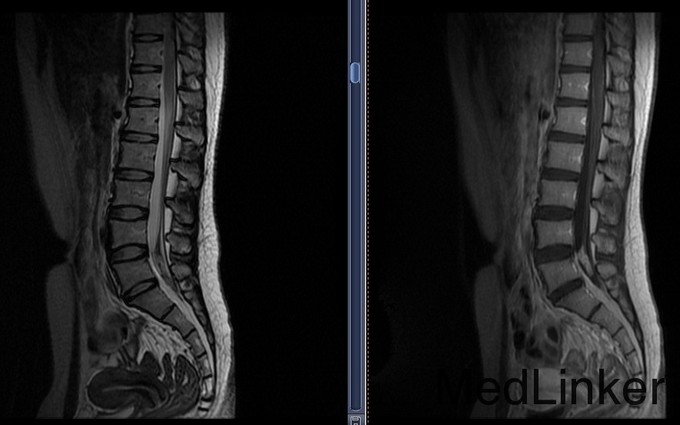

患者,女,F,19岁。以“腰腿痛20余天,缓解10天”为主诉入院。患者于20余天前无明显诱因突发腰部伴双下肢疼痛,疼痛呈阵发性,发作无规律,活动时加重,休息可缓解.无麻木和四肢无力等伴随症状.患者于2015年9月10日就诊于XX中心医院,行腰椎CT、腰椎MR及腰椎增强MR检查,提示L5水平椎管内异常强化灶。未予治疗。近10天,患者疼痛症状明显缓解。患者为求治疗,今日来我院,门诊以“腰椎管内占位”为诊断将患者收入我科。患者患病以来,精神状态可,饮食睡眠可,二便正常,体重无明显变化。

入院查体:T 36.5℃,P 90次/分, BP 116/70mmHg, R18 次/分.神志清,查体合作,营养发育良好,步入病房,浅表淋巴结未触及肿大.头颅大小正常,双瞳孔等大正圆,对光反射灵敏。四肢活动自如,肌张力正常,双上肢肌力V级,双下肢肌力IV,深浅感觉未见明显异常,双侧巴氏征阴性。Romberg征(-)。外院MR增强提示:L5水平椎管内异常强化灶。

患者病史较短,仔细追问腰痛期间曾有发热,科内讨论会诊不除外炎症或出血机化。安排手术后暂停,经过再次讨论和家属交待手术风险后决定手术探查。 腰后正中入路,椎管内占位病变探查切除术; 原手术方案拟行椎弓根固定,但术中病理提示不除外脊索瘤,考虑术后可能需放疗,遂放弃固定治疗。 术后石蜡病理为粘液乳头型室管膜瘤(WHOⅠ级)

随访:患者术后复查MR肿瘤完整切除,2周顺利出院,无运动、感觉及二便副损伤。 讨论:1.患者年轻女性,反复发热腰痛起病,病史不长,此类椎管内异常影像应考虑到炎症、出血等良性疾病可能,在充分向家属告知基础上方可手术探查。否则易出现纠纷。2.室管膜瘤(WHOⅠ级)多数预后良好,可不行后续放化疗,嘱患者定期门诊随访。